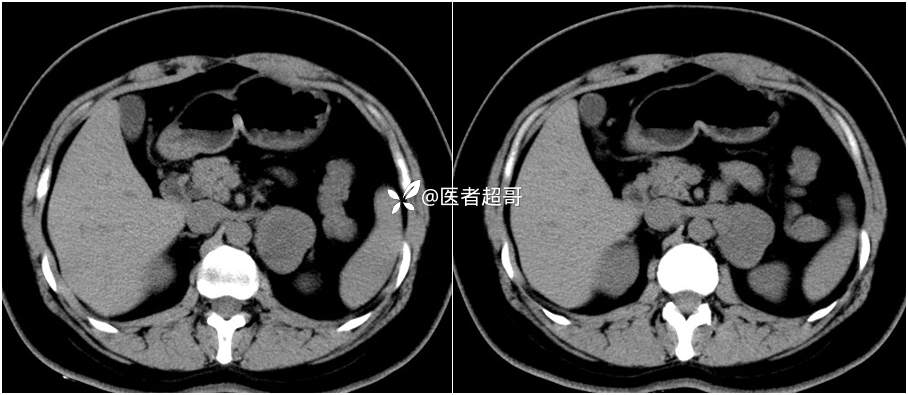

病例【影诊笔记711】女,23岁,体检发现左侧肾上腺占位,有病理,请赏析~~~

女,23岁,体检发现左侧肾上腺占位